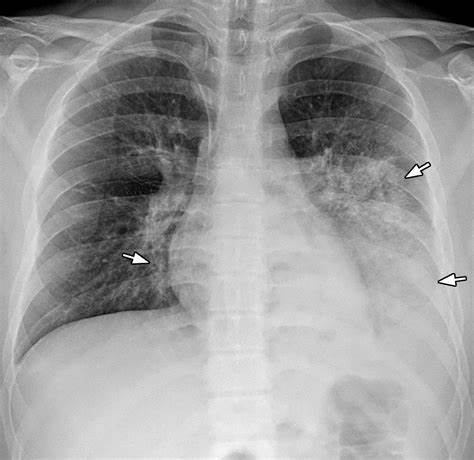

ChestExpert Prime

Our flagship AI diagnostic system for detecting 14 chest abnormalities from X-ray images with radiologist-level accuracy. Trusted by healthcare professionals worldwide.

Comprehensive Chest Analysis

ChestExpert Prime leverages advanced deep learning to analyze chest X-rays with precision and speed, detecting 14 critical abnormalities — including pneumonia, tuberculosis, pneumothorax, and cardiac enlargement. Trained on more than 500,000 expertly annotated radiographs and rigorously validated, it delivers clinically reliable well drafted xray reports and insights to support faster, more confident decision-making at the point of care.